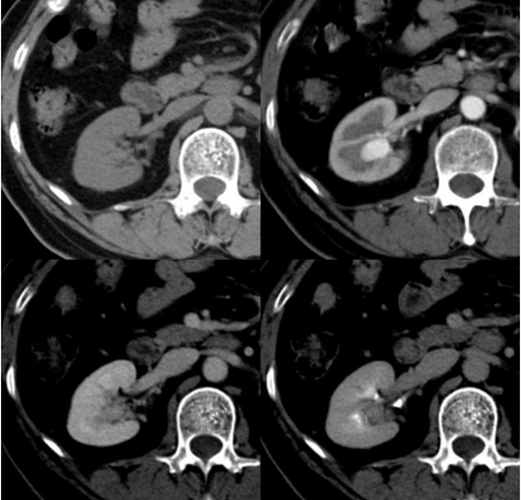

糖尿病腎病變圖片

糖尿病腎病症狀